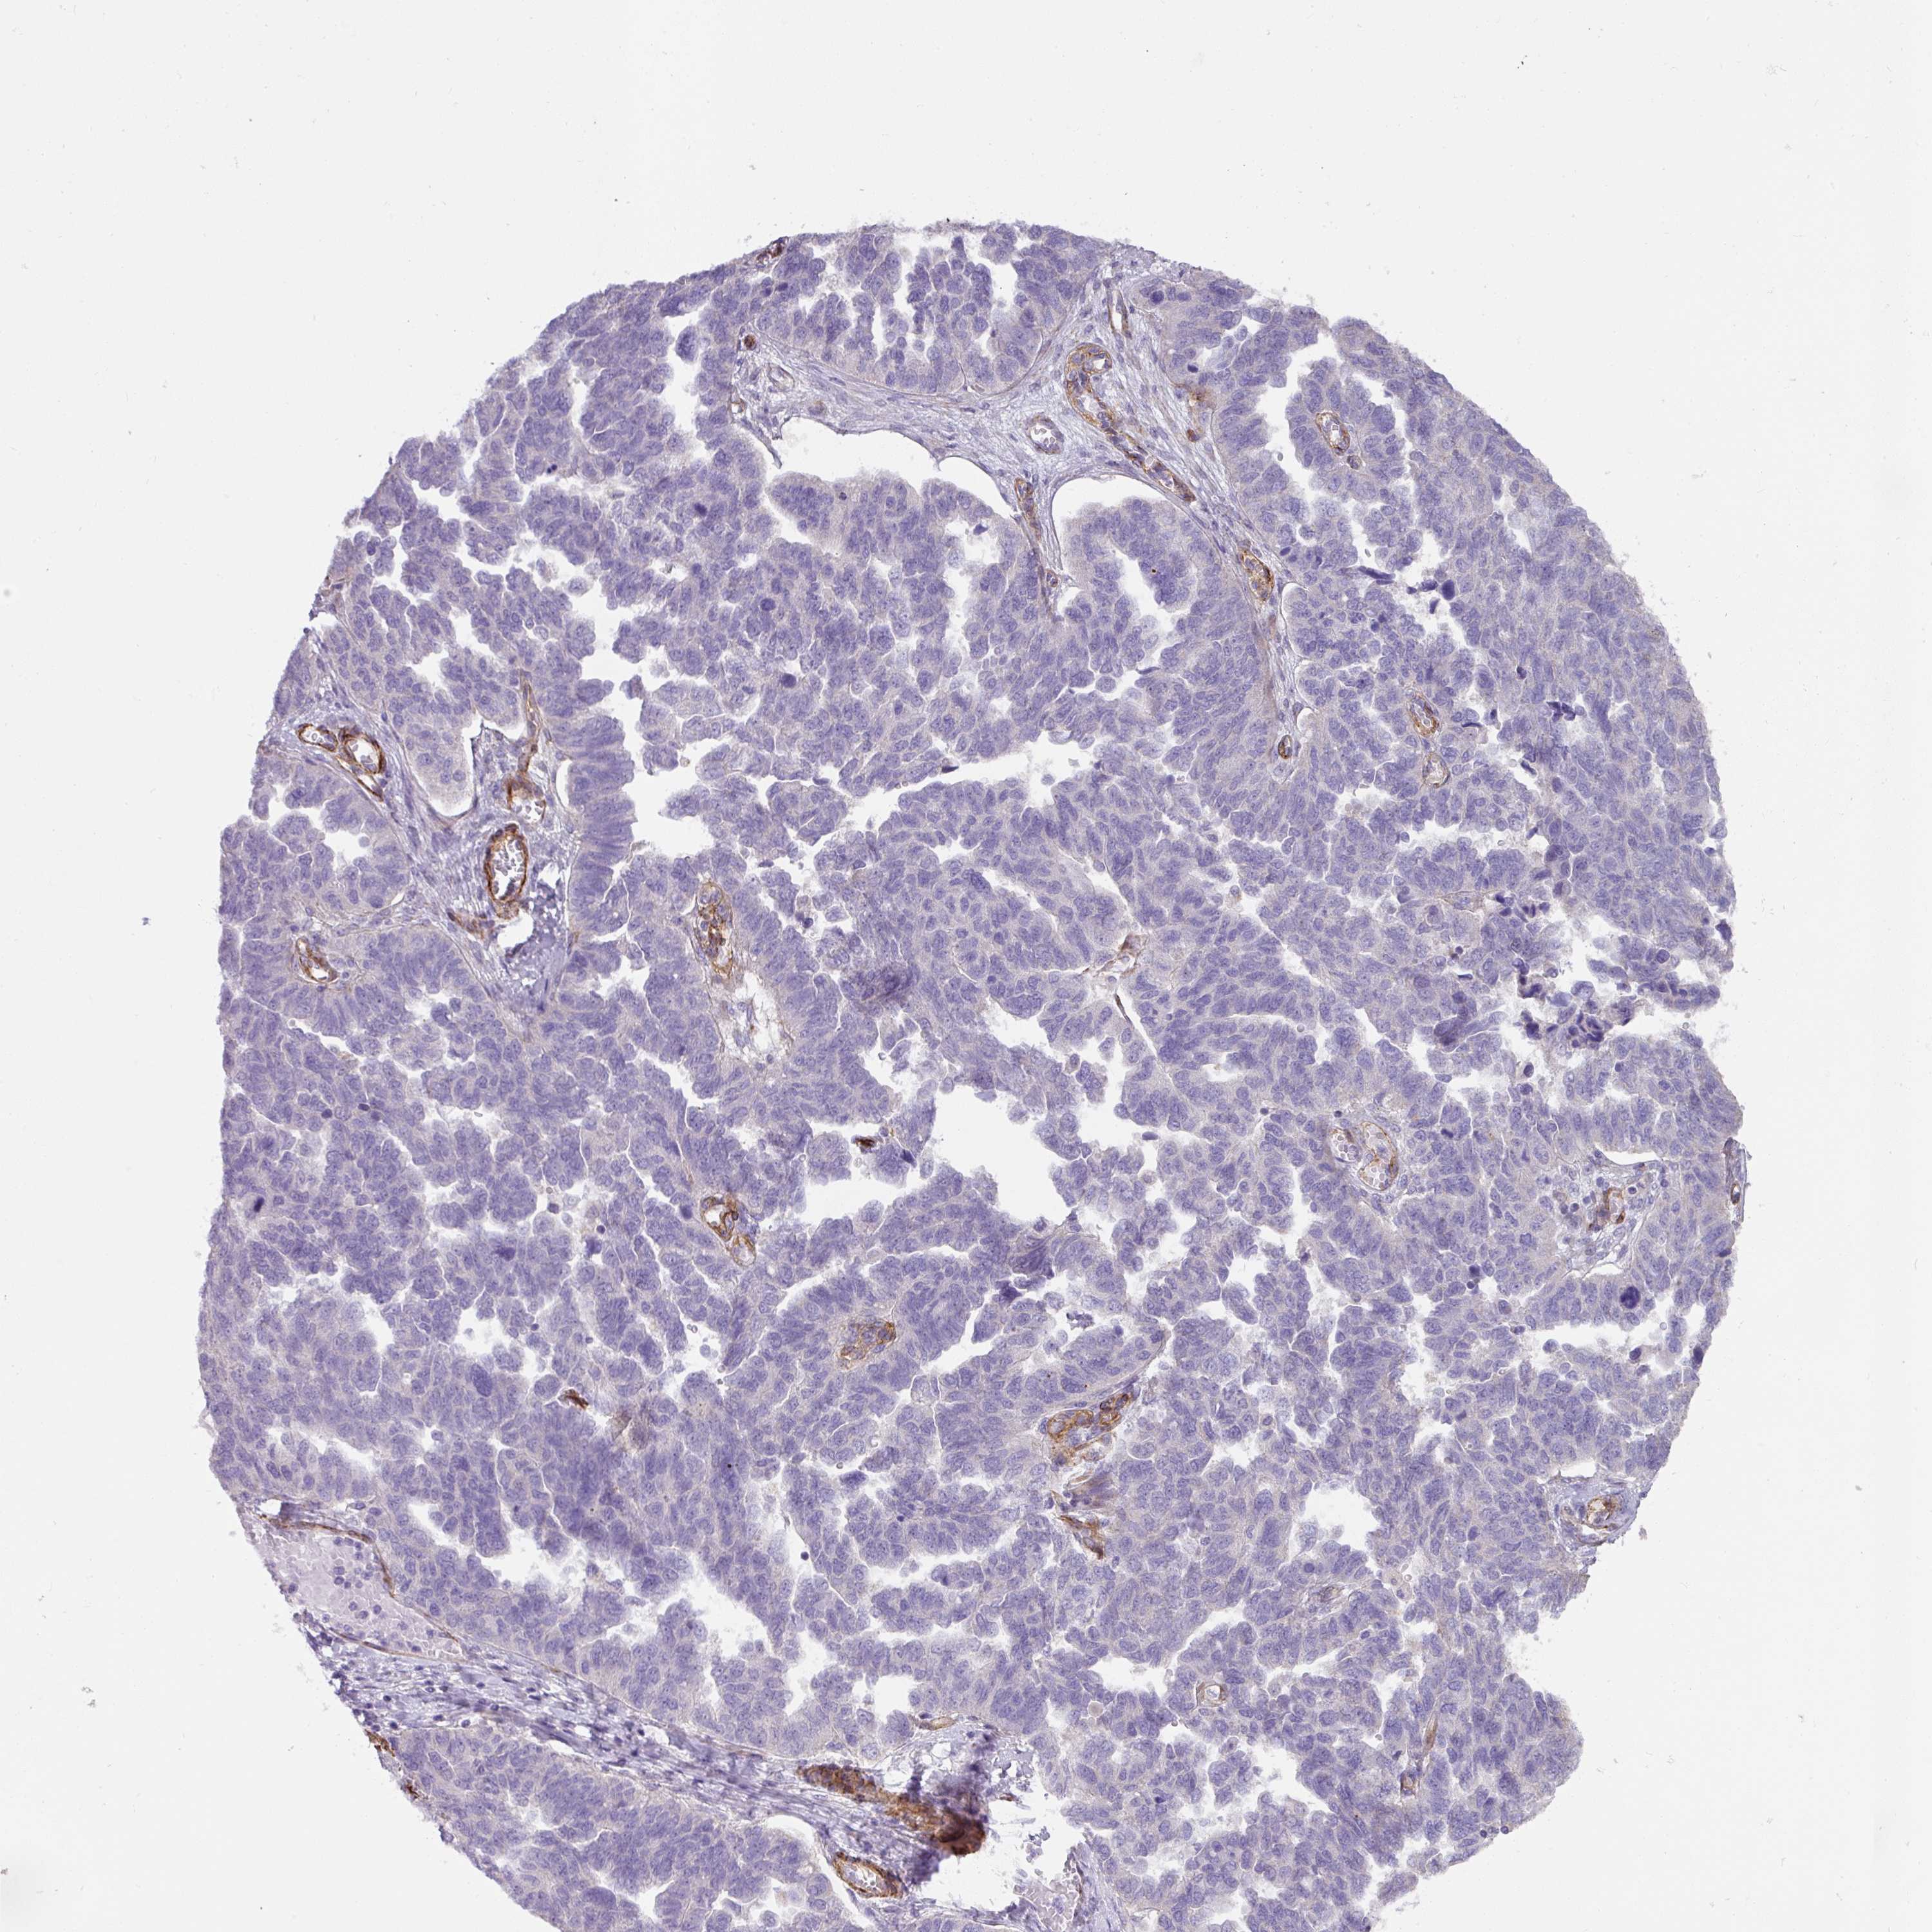

OVARIAN CANCER - Protein expressioni

A mouse-over function shows sample information and annotation data. Click on an image to view it in a full screen mode. Samples can be filtered based on level of antibody staining by selecting one or several of the following categories: high, medium, low and not detected. The assay and annotation is described here.

Note that samples used for immunohistochemistry by the Human Protein Atlas do not correspond to samples in the TCGA dataset.

Antibody stainingi

Antibody staining in the annotated cell types in the current human tissue is reported as not detected, low, medium, or high, based on conventional immunohistochemistry profiling in selected tissues. This score is based on the combination of the staining intensity and fraction of stained cells.

Each image is clickable and will lead to virtual microscopy that enables deeper exploration of all samples and also displays staining intensity scores, fraction scores and subcellular localization as well as patient and tissue information for each sample.

Antibody HPA052708

Staining

High

Medium

Low

Not detected

Intensity

Strong

Moderate

Weak

Negative

Quantity

>75%

75%-25%

<25%

None

Location

Nuclear

Cytoplasmic/membranous

Cytoplasmic/membranous,nuclear

Cystadenocarcinoma, serous, NOS

Cystadenocarcinoma, mucinous, NOS

Adenocarcinoma, NOS

Carcinoma, endometroid